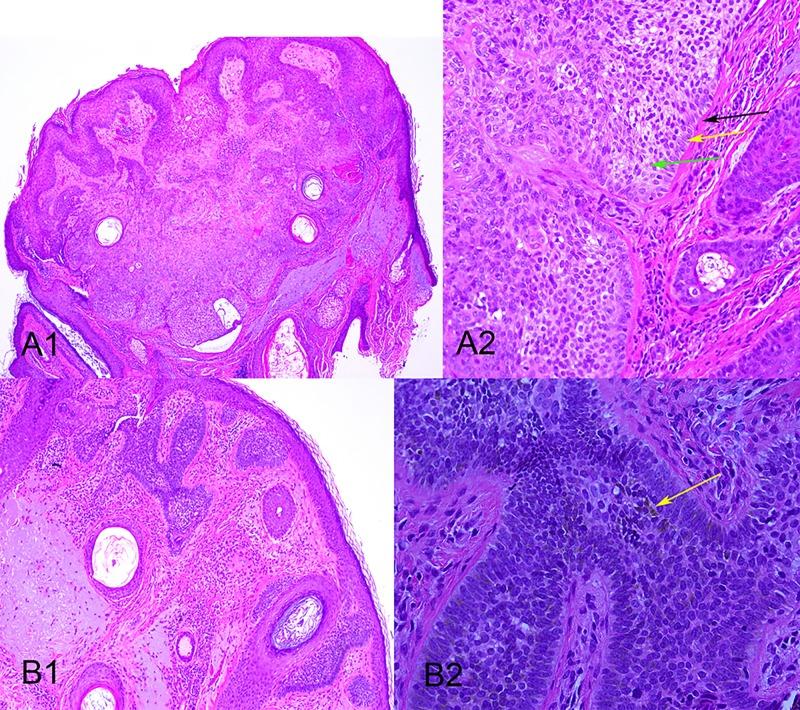

Trichilemmoma in continuity with pigmented basal cell carcinoma; with dermatoscopy and dermatopathology.

A case of trichilemmoma in continuity with a pigmented basal cell carcinoma is presented with dermatoscopy and dermatopathology. The distinction between the two lesions was evident dermatoscopically and was confirmed dermatopathologically. While trichilemmoma has been reported in association with basal cell carcinoma and dermatoscopy images of four previous cases of trichilemmoma have been published, no previous dermatoscopy image has been published of trichilemmoma associated with basal cell carcinoma.